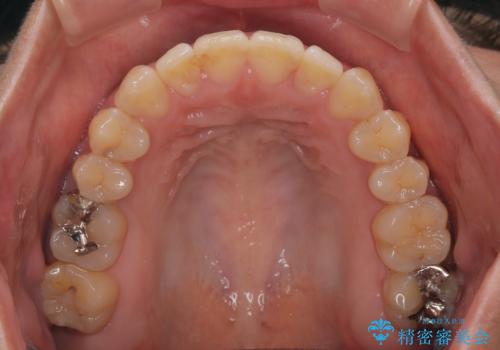

- 極端な開咬を気にして来院された患者様です。

開咬の方の特徴として、幼少期の指しゃぶりの癖や、強い舌の突出癖が挙げられます。

こちらの患者様も強い舌の突出癖が認められたため、矯正治療を行うにあたり、舌のトレーニングをしっかりと行っていただくように指示をいたしました。

開咬はインビザラインが得意とする歯列不正であるため、舌のトレーニングを行いながら、インビザラインにて矯正治療を行うこととしました。

担当医としては、もっと上下の前歯を接触させるところまで治療を進めたいという思いがありますが、今まで咀嚼できなかったものが食べられるようになったということで、この状態で治療終了となりました。